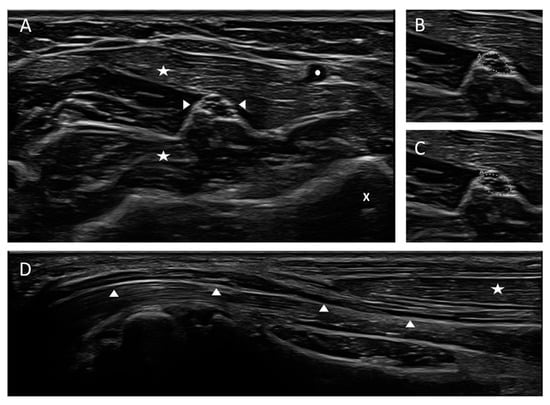

- Dorner, M.; Schreiber, F.; Stephanik, H.; Tempelmann, C.; Winter, N.; Stahl, J.H.; Wittlinger, J.; Willikens, S.; Kramer, M.; Heinze, H.J.; et al. Peripheral Nerve Imaging Aids in the Diagnosis of Immune-Mediated Neuropathies-A Case Series. Diagnostics 2020, 10, 535. [Google Scholar] [CrossRef]